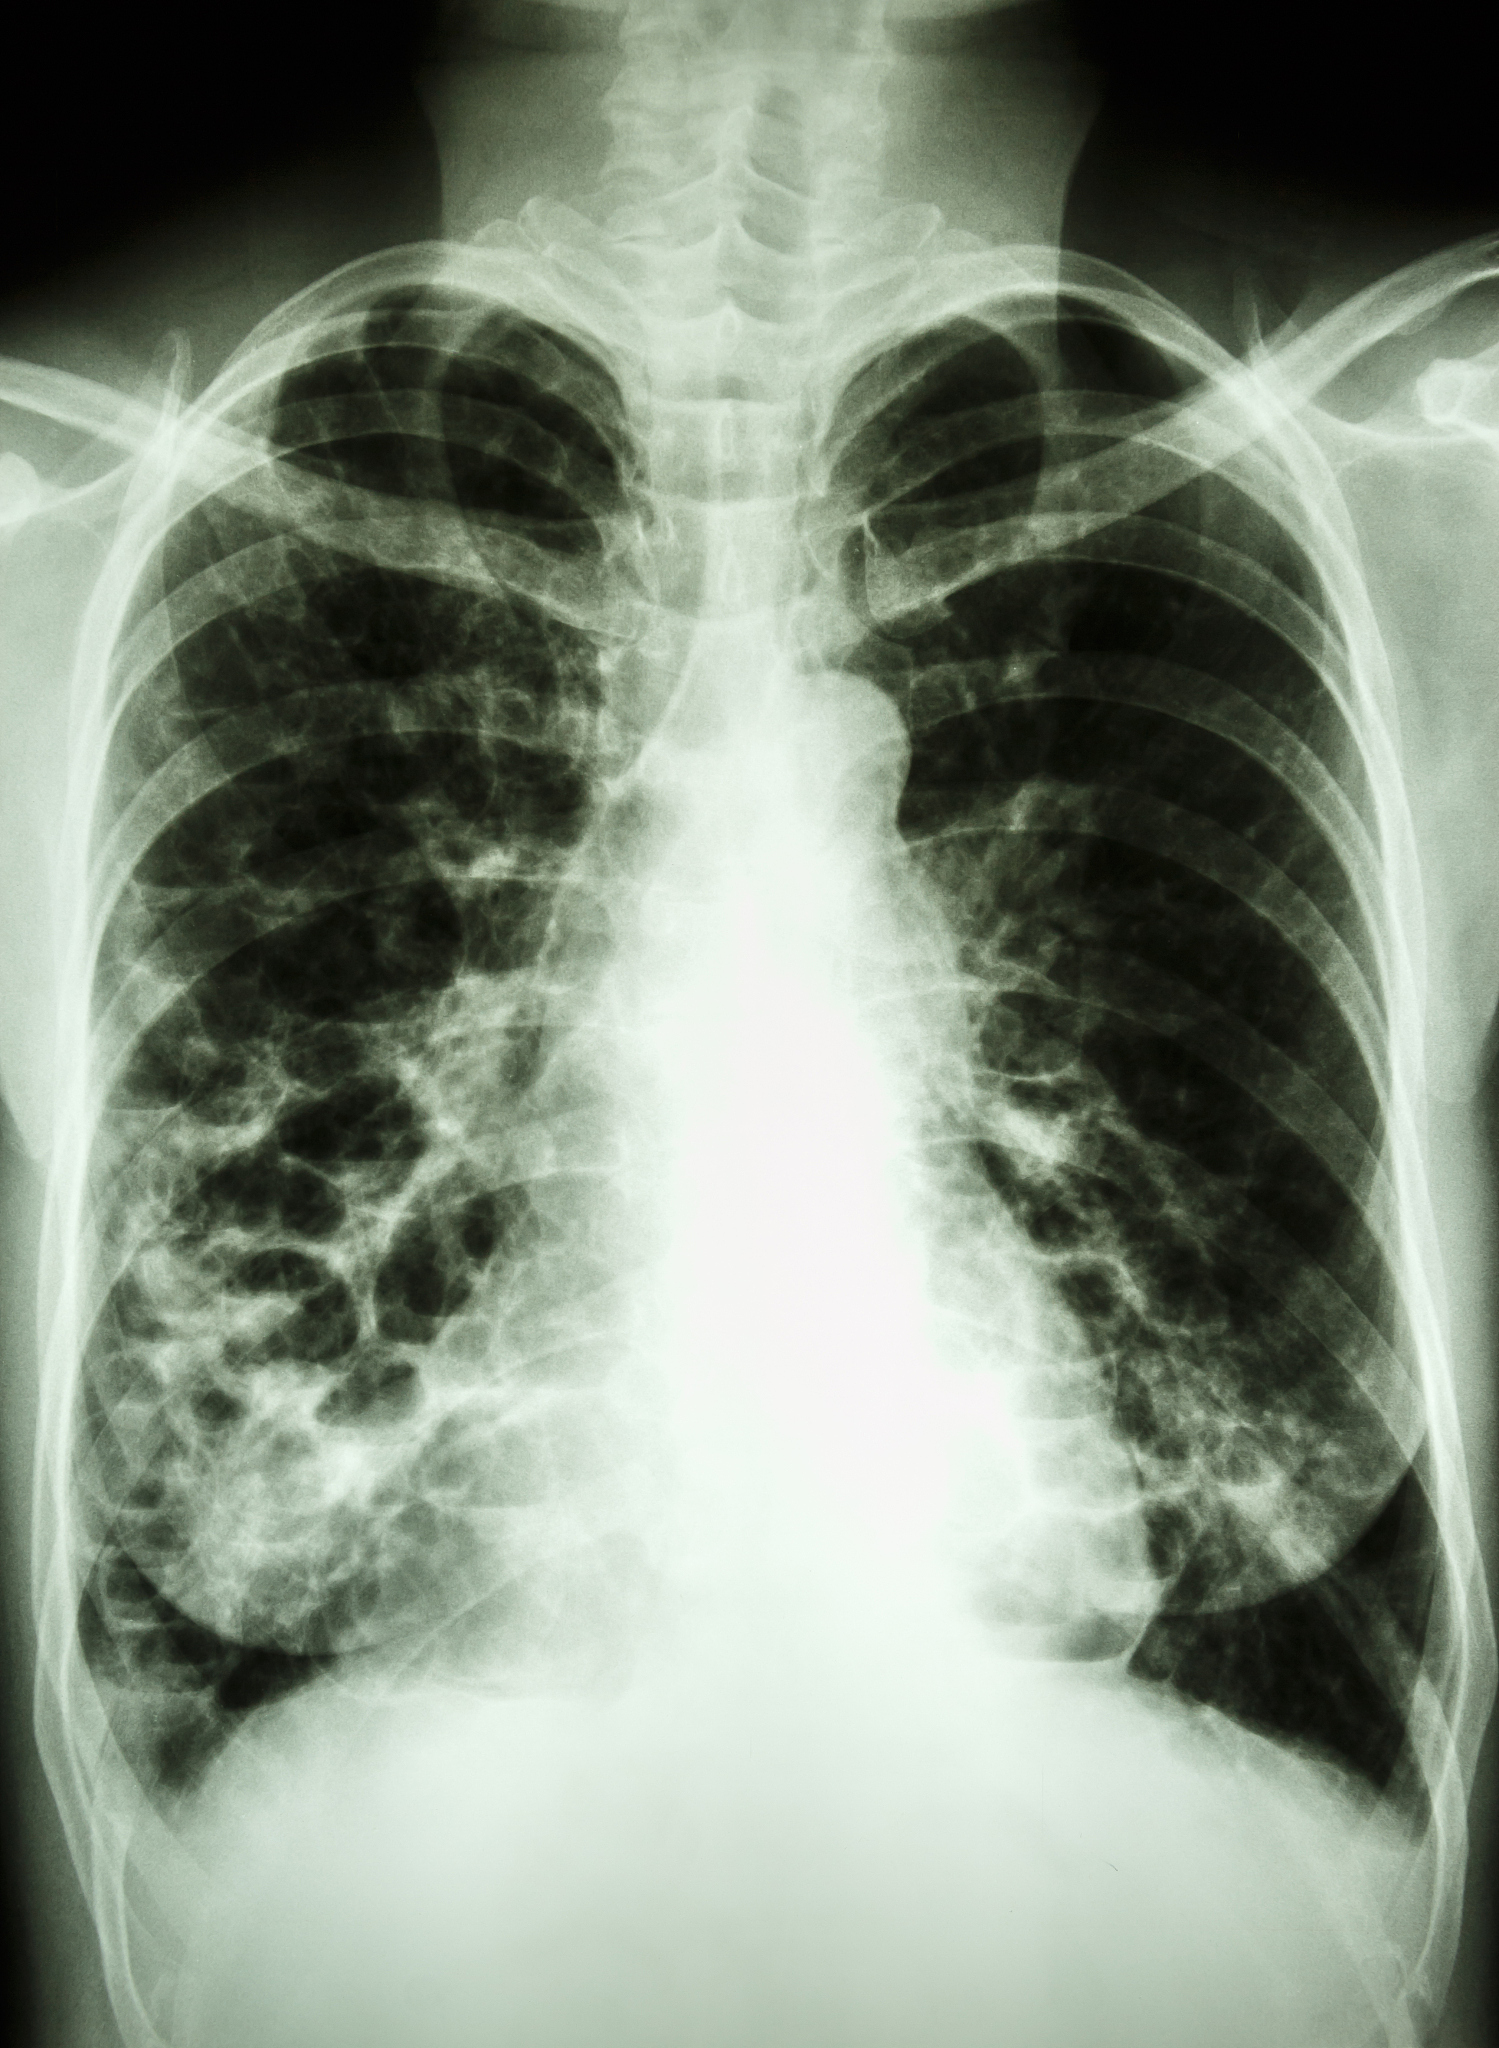

普米克是一种常用的雾化药物,主要用于治疗哮喘和慢性阻塞性肺疾病(COPD)等呼吸系统疾病。以下情况下可以考虑使用普米克做雾化:

1. 哮喘急性发作:普米克可以通过雾化吸入快速缓解哮喘症状,减轻呼吸困难等不适感。

2. COPD急性加重:普米克可以通过雾化吸入缓解COPD急性加重症状,如咳嗽、气促等。

3. 慢性支气管炎:普米克可以通过雾化吸入减轻慢性支气管炎引起的症状,如咳嗽、痰多等。

4. 支气管扩张试验:普米克可以通过雾化吸入进行支气管扩张试验,帮助医生诊断哮喘和COPD等呼吸系统疾病。